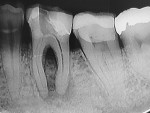

A 45-year-old man was referred for the endodontic treatment of his mandibular left first molar. Sensitivity tests were negative, but the patient presented with swelling and a sinus tract. The tooth was diagnosed as necrotic with chronic apical periodontitis. An extended interradicular and periapical lesion was also observed during the radiographic evaluation (Figure 1). At the first appointment, the patient was anesthetized using lidocaine with 1:100,000 epinephrine (Alphacaine, DFL Indústria e Comércio S/A), and the canals were instrumented with a series of rotary NiTi files (Bassi Logic™ Shaping & Glidepath Files, Bassi Endo) up to size 30/.05 and irrigated with a 2.5% sodium hypochlorite (NaOCl) solution. After a 17% ethylenediaminetetraacetic acid (EDTA) solution was applied for 60 seconds, the canals were filled with calcium hydroxide, and it was left in place for 15 days until the next appointment.